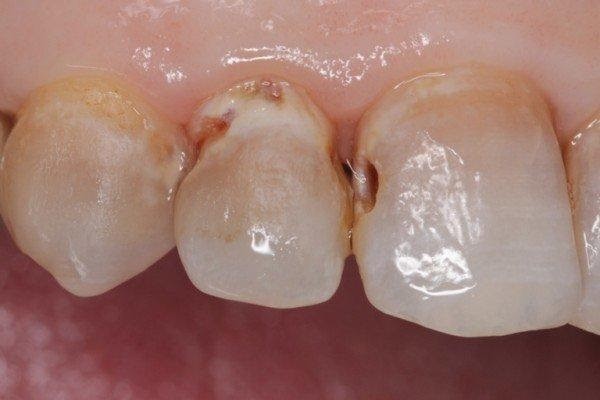

Sâu kẽ răng là tình trạng ở giữa 2 kẽ răng có những lỗ sâu nhỏ. Chúng có thể xuất hiện ở kẽ răng mặt ngoài hoặc mặt trong của răng. Sâu kẽ răng là bệnh lý khá phổ biến và có thể gặp ở mọi đối tượng.

(Sâu kẽ răng là bệnh lý thường gặp)(**)

Đây là giai đoạn đầu (giai đoạn khởi phát) của bệnh sâu kẽ. Dấu hiệu nhận biết bệnh thường chưa rõ ràng.Khi quan sát kỹ bạn sẽ thấy có xuất hiện các vệt trắng hoặc đen rất nhỏ ở giữa 2 kẽ răng

Vi khuẩn tấn công lớp men răng và thâm nhập đến lớp ngà nông tạo thành các lỗ nhỏ li ti trên răng

Đây là giai đoạn nghiêm trọng của bệnh lý. Men răng và ngà răng đã bị ăn mòn. Vi khuẩn gây sâu răng sẽ tiếp tục thâm nhập vào tủy răng có thể gây viêm tủy, viêm nướu và thường xuất hiện những cơn đau răng dữ dội.